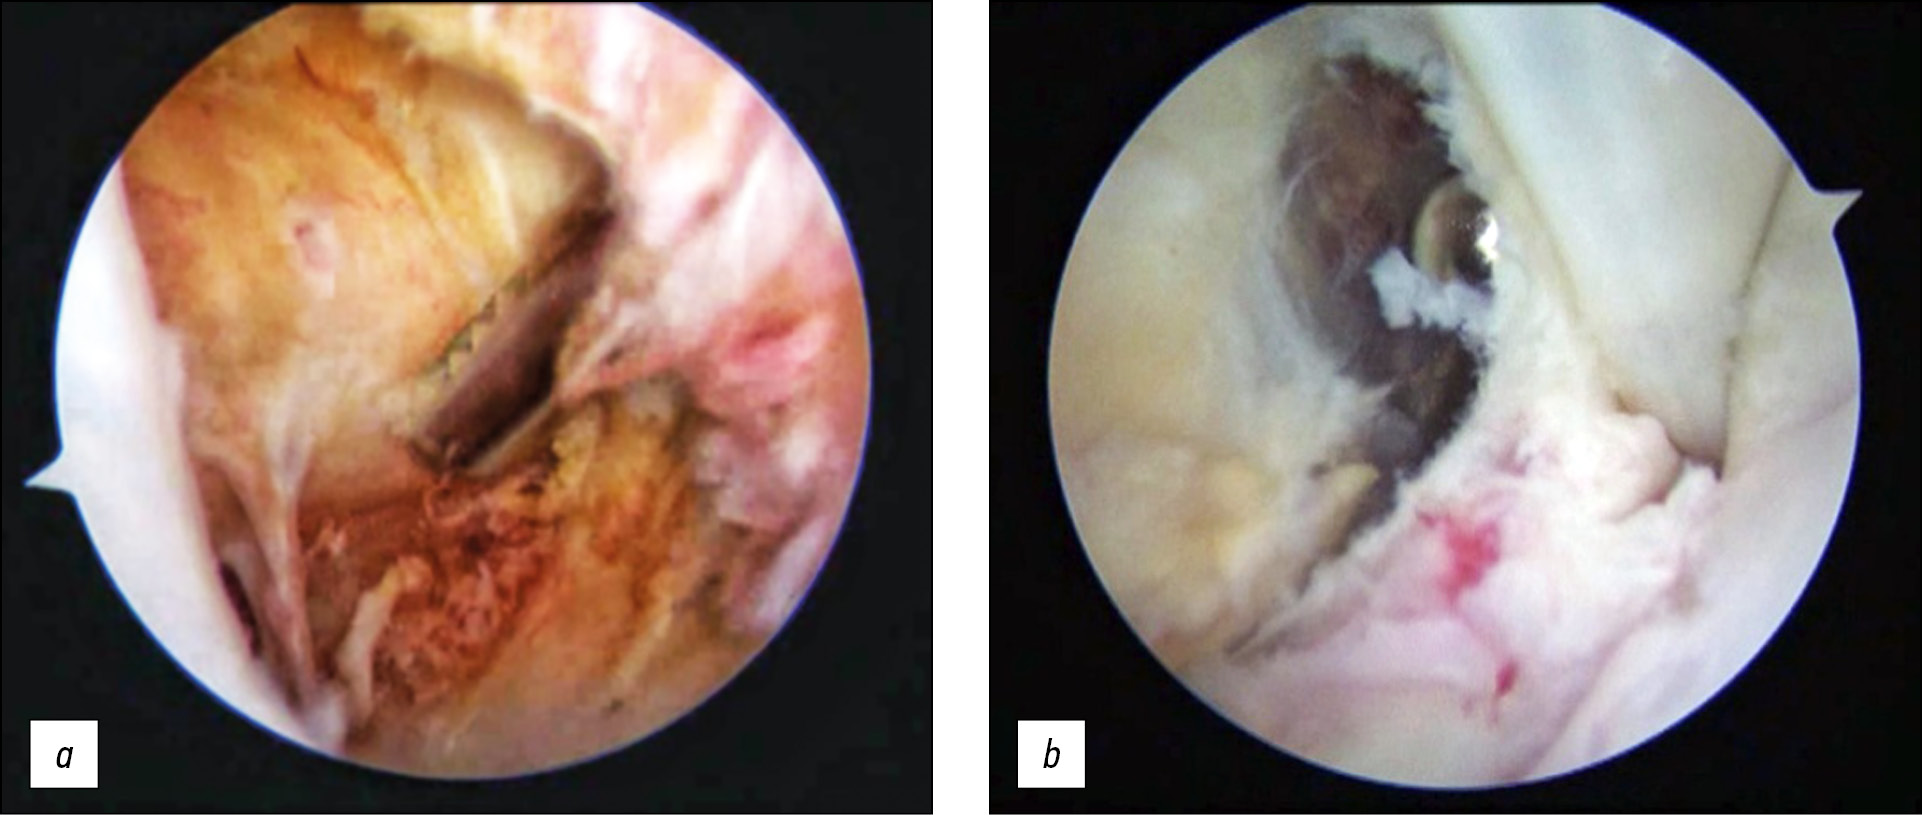

Then, the joint capsule was mobilized, the rotator interval was widened using a shaver and a coblator, degenerative areas of the articular lip and the acromioclavicular ligament were resected in the anterior–inferior section through the 5 o’clock position (Fig. 5).

Fig. 5. Treatment of a safe rotatory interval with a shaver and coblator: a — access implementation; b — mobilization of the capsule and expansion of the rotator interval.